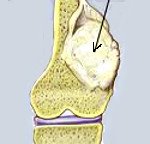

Кроме того у остеосаркомы существуют «излюбленные» места расположения в каждой отдельной кости. Так, у бедра обычно поражается дистальный конец, у большеберцовой кости - внутренний мыщелок, у плечевой - область, где расположена шероховатость дельтовидной мышцы.